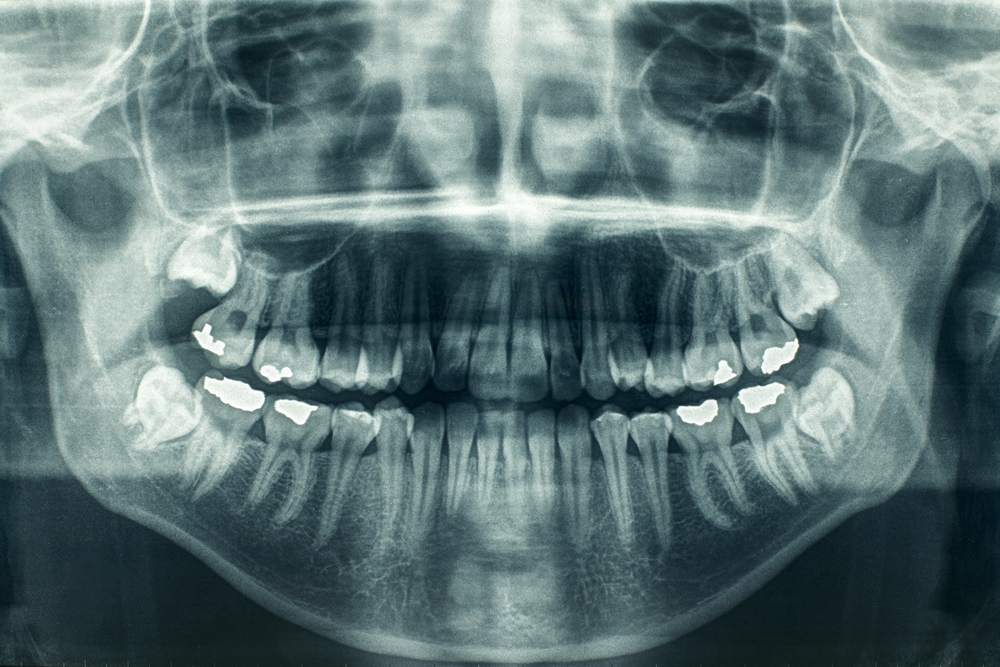

Existing traditional dental fillings are toxic to human cells and therefore not compatible with the pulp tissue found inside the tooth. In the case of dental pulp disease/injury, root canals are necessary to remove the infected tissue, which if left untreated can actually spread to the sinus and brain and, in rare cases, result in death.

The scientists developed a new kind of filling; one made from synthetic biomaterial that can stimulate the growth of stem cells in the pulp of the tooth. Applied just like regular fillings, researchers believe that if used in a damaged tooth, those stem cells can repair the kind of damage that often comes from the installation of a filling. In essence, the biomaterial filling would allow the tooth to heal itself.